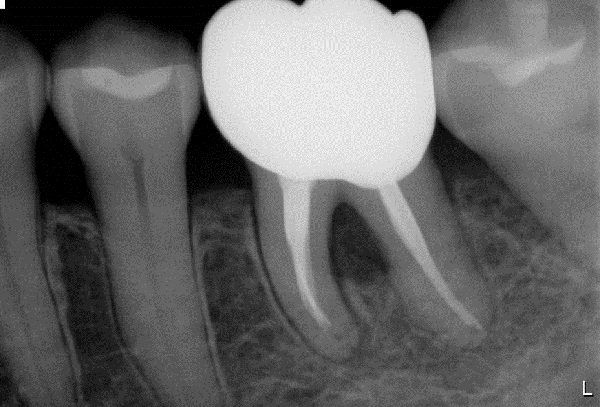

軽度〜中程度レベルの歯周炎であれば、ここで改善が見られますが、中程度以上の歯周炎の場合は、その後に歯周外科処置を行うことが多いです。なぜなら、歯周ポケットが5mm以上ある部位にSRPを行っても多くの歯石の取り残しがあるという報告があるため、深い歯周ポケットを有する患者さんに対しては歯周外科処置を行います。歯周外科処置で一般的な術式は歯肉剥離掻爬術です。痛く無いように麻酔(局所麻酔)をした後、歯肉をメスで切り(切開)、切った歯肉を骨から剥がし(剥離)、歯の根に付着した歯石、歯槽骨の形態などが直接見える状態で、歯石や感染物の除去を行います。その際必要であれば、その後に患者さん自身で清掃がしやすいように骨の形態を整える歯槽骨整形も行います。最後に切った部分を縫って(縫合)処置を終わります。

歯周組織再生療法といい、先に記しました通り、GTR法、エムドゲインを使用した方法、リグロスを使用した方法といくつかあります。GTR(Guided Tissue Regeneration)法とは、歯周外科処置と同様に歯肉をメスで切り(切開)、切った歯肉を骨から剥がし(剥離)、歯の根に付着した歯石、歯槽骨の形態などが直接見える状態で、歯石や感染物の除去を行います。その後、骨が吸収して失われた部分にこのバリア膜で覆い縫って(縫合)処置を終わります。バリア膜で覆うことで、歯肉などの軟組織が骨の中へ直接入り込むことを防ぎ、新しい血管が新生され、歯周組織の再生を促します。治療後およそ6ヶ月待ちます。